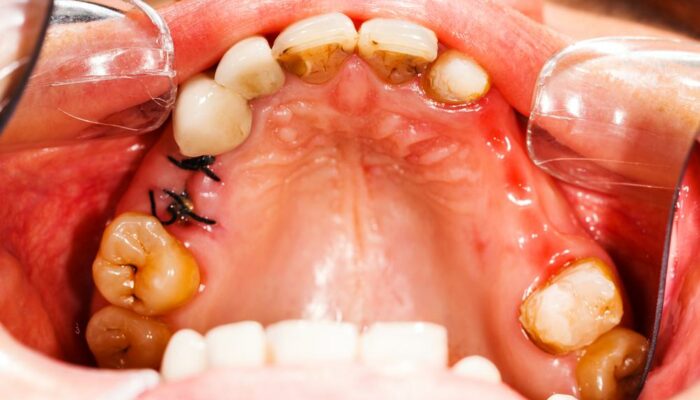

Caries, the other word for cavities, can be defined as the small holes or openings in the teeth that are a result of decaying tooth. To be able to know as to how to treat cavities, first, it’s important to know the causes of cavities. Cavities are a result of plaque and bacteria that builds its home on the teeth’s surface.

In order to be able to treat cavities, it is important to be aware of the signs& symptoms of cavities. Once you have recognized the following signs, commence the treatment without further delay. This will help you save your tooth and will also help get rid of the constant pain and sensitivity that one experiences if he or she has cavities.

Following are the symptoms of cavities

- Be subjected to toothache or sensitivity.

- Experiencing mild to sharp pain while eating or drinking something hot or cold.

- Experiencing pain while biting food.

- Dark-stained pits and holes on the tooth/teeth.

- Breaking or chipping of the teeth, thus exposing a black inner surface.

There are some cavities, not visible to the naked eye that reside at the back of the mouth or between teeth. Now these cavities, although, don’t cause pain, can be identified only through ultrasound, x-rays, and/or fluorescent lighting. Therefore, it is extremely important to see your dentist regularly in order to keep your teeth in good health.